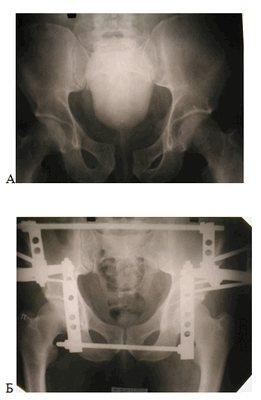

Аппарат внешней фиксации должен обладать широким диапазоном репонирующих возможностей и обеспечивать надежную фиксацию таза. Отвечает этим требованиям разработанный аппарат внешней фиксации для лечения повреждений тазового кольца со смещением (рис. 2).

Рисунок 2. Клинический пример. А - рентгенограмма до операции; Б - рентгенограмма после оперативного вмешательства

Особенность его заключается в формировании опоры на подвздошных костях, причем по 2 стержня устанавливают в надацетабулярную область, в проекции нижнего полюса крестцово-подвздошного сочленения. По 2 стержня устанавливают в гребни подвздошных костей. При свежих повреждениях и переломах достаточно и 3 стержней, корректно установленных через гребень подвздошной кости. Стержни крепят к опоре, монтируемой из комплектующих аппарата Илизарова. После этого производится репозиция и стабилизация таза в аппарате. При этом, наряду с другими повреждениями тазового кольца, стабилизируется и воссозданный свод таза.